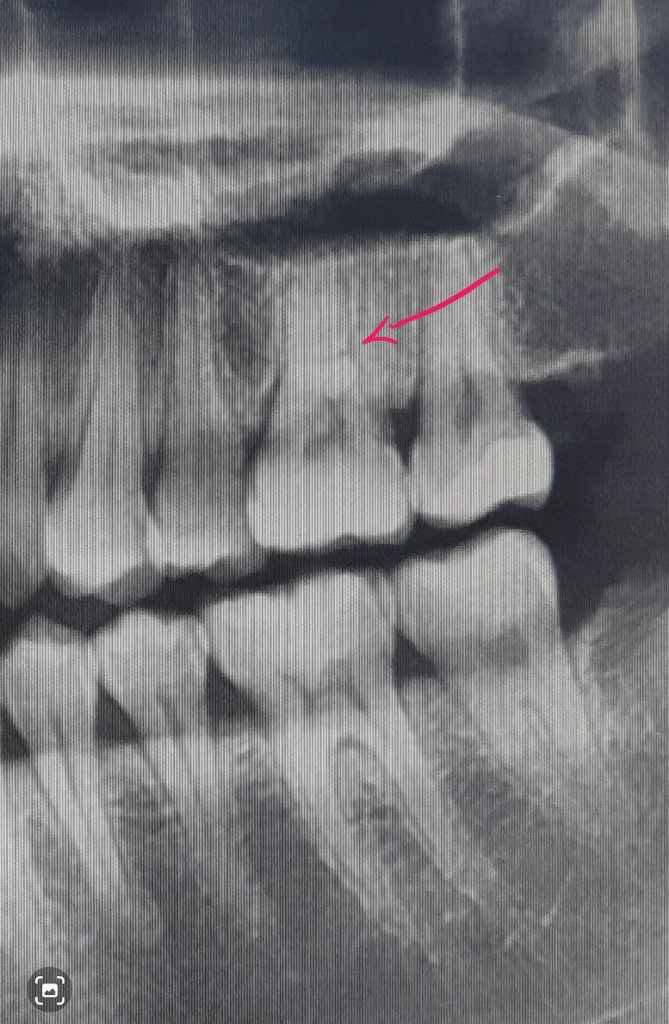

혹시해서 파노라마확인했는데

화살표 표시된곳은 크랙인가요??

저 치아가 칫솔닿이면 시린치아입니다

파노라마에서 치과에서는 별말없었는데...

사진에서 가리키는 부분은 치아에 뿌리가 분지되는 부분입니다 크랙의 형태로는 보이지 않기 때문에 크게 걱정하지는 않으셔도 됩니다.

1. 방사선 사진상 해당 치아 치수강 위축 (신경이 있는 관의 크기가 작아짐)이 이뤄진 것으로 보아 어떤 자극이 치아에 지속적으로 가해졌던 것 같습니다. 그 자극은 충치일 수도 있고 딱딱한 음식을 즐겨 드시어 교합력이 과도하게 작용해서 그랬을 수도 있고요. 후자의 경우 치아 금이 간 것과 연관될 수 있습니다.

2. 뿌리쪽 금이 간 경우는 치료가 힘들 수도 있습니다. 신경치료를 하고 치아를 보호하기 위해 크라운을 씌운다해도 결과적으로 증상이 개선되지 않을 수도 있습니다.